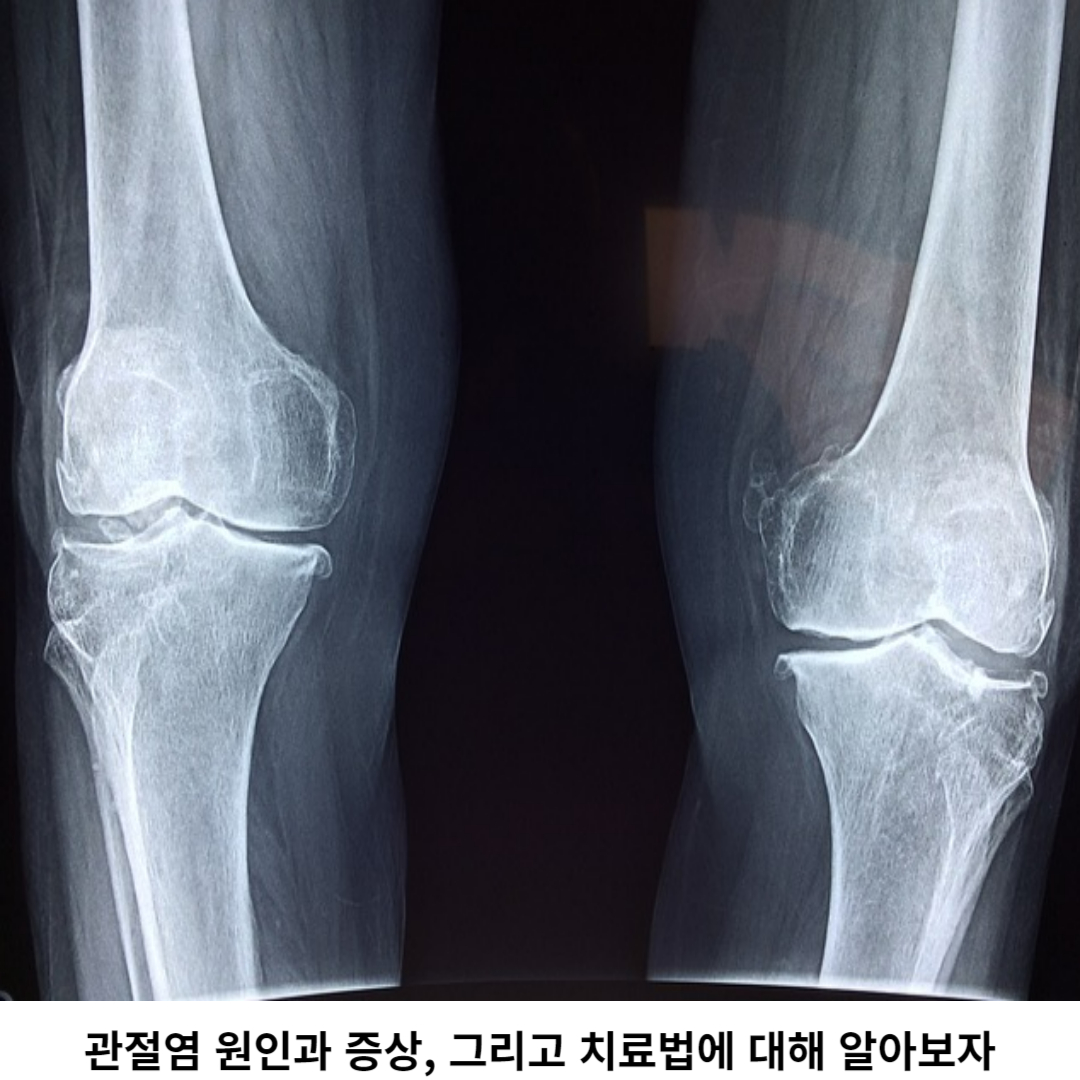

관절염은 완전한 치료는 어렵지만, 증상 완화와 진행 억제를 위해 여러 가지 치료법이 존재합니다. 약물 치료는 관절염의 증상을 완화하는 데 가장 일반적으로 사용되며, 통증 완화와 염증 억제를 위해 진통제와 항염증 약물이 사용됩니다.

진통제 통증을 완화하여 일상생활 활동에 도움이 되며, 항염증 약물은 염증을 줄어들게 하여 관절 손상을 줄일 수 있습니다. 물리치료와 운동 요법은 관절의 움직임을 향상하고 근력을 강화하는 데 도움이 됩니다.

물리치료는 열, 냉기, 운동 치료, 전기 자극 등 여러 가지 치료 법을 포함할 수 있습니다. 이러한 치료법은 관절의 유연성을 향상하고 통증을 완화하는 데 도움을 줄 수 있습니다.

또한, 관절을 정상화시키기 위해 보조기구 사용이 권할 수도 있습니다. 보조기구는 관절에 가해지는 힘을 감소시켜 통증을 완화시키고 관절의 안정성을 높여 줍니다. 또한, 건강한 식습관과 체중 관리도 관절염 치료에 중요한 보조 역할을 합니다.

비만은 관절에 압력을 증가시키므로, 체중 감량을 통해 증상을 줄일 수 있으며 도움이 됩니다. 관절에 안정감을 찾기 위해 일정한 휴식과 일상생활에 균형을 유지하며, 컨디션을 찾는 것이 중요합니다.

심각한 관절 손상이 있는 경우 수술은 피할 수 없습니다. 관절 대체 수술은 관절을 완전히 교체하는 것으로, 고령자나 관절에 심한 손상이 있는 환자들한테 진행을 합니다.

이 수술은 관절의 통증 완화와 움직임에 도움을 줄 수 있습니다. 관절 접근 수술은 관절 주위의 손상된 조직을 제거하고, 관절의 안정성을 향상하기 위해 수술로 대체하는 것입니다.